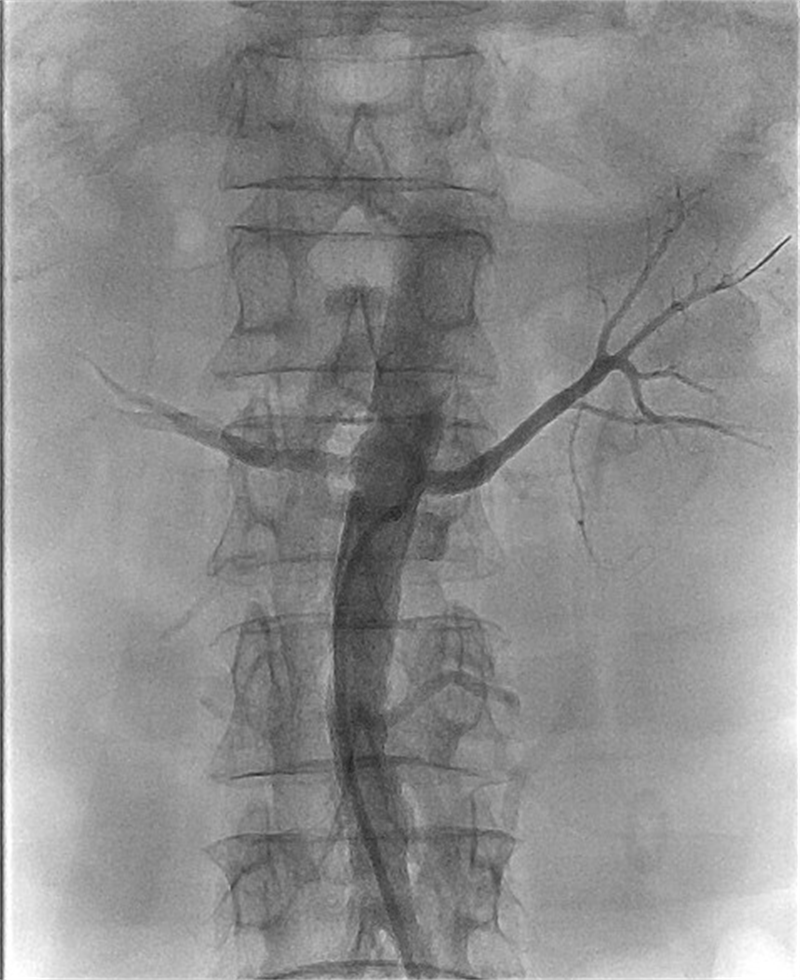

介入医学科团队会诊后,经过详细的术前讨论与准备,决定科主任胡鸿为其实施肾动脉造影球囊扩张支架植入微创手术。术中,胡鸿从杨先生右侧股动脉穿刺置入鞘管,再用微导丝小心翼翼地穿过狭窄的血管,接着用球囊扩张支架成功撑开了狭窄的血管,让肾脏的供血得到明显改善,从根源上消除了导致血压升高的罪魁祸首。术后,杨先生的血压逐渐降了下来。如今,他情况稳定,只需要口服一种降压药,就能把血压控制得很好。

| 术中植入支架 |